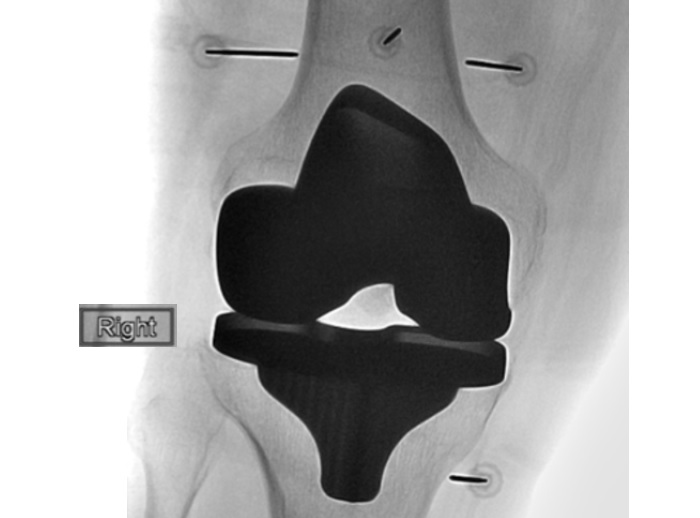

La douleur arthritique du genou est une cause majeure d'invalidité. Aux seuls Etats-Unis, plus de 14 millions de personnes en souffrent avec des symptômes sévères dont une douleur intense et une perte de mobilité qui entraîne, dans de nombreux cas, une perte d’autonomie. Une technique émergente et peu invasive, l’ablation par radiofréquence et par le froid (crypothérapie) (C-RFA pour cooled radiofrequency ablation) démontre ici son efficacité à soulager la douleur après une arthroplastie du genou. C’est la démonstration apportée par cette étude pilote, de suivi de 21 patients, présentée aux sessions scientifiques de la Radiological Society of North America (RSNA) 2021.

Un nombre croissant de patients souffrant d’arthrose du genou optent pour une arthroplastie totale du genou, ou son remplacement, dans le but de retrouver une mobilité normale et de récupérer en qualité de vie. Dans la réalité, 15 à 30 % des patients ayant subi cette arthroplastie continuent de ressentir de la douleur et à souffrir de raideur au genou. Les médecins peuvent dans certains cas leur proposer une nouvelle intervention chirurgicale, mais sans garantie de pouvoir éradiquer définitivement la douleur. « De très nombreux patients continuent à éprouver de la douleur », précise l'auteur principal, le Dr Felix Gonzalez, professeur d'imagerie musculosquelettique à l'Université Emory (Atlanta, Géorgie).